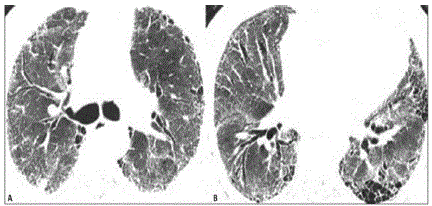

Você está diante de um paciente portador de fibrose pulmonar idiopática, última tomografia mostrada abaixo, com prognóstico reservado em relação à doença de base, familiares conscientes da situação. Diante do quadro de exacerbação aguda da doença, o que é melhor indicado?